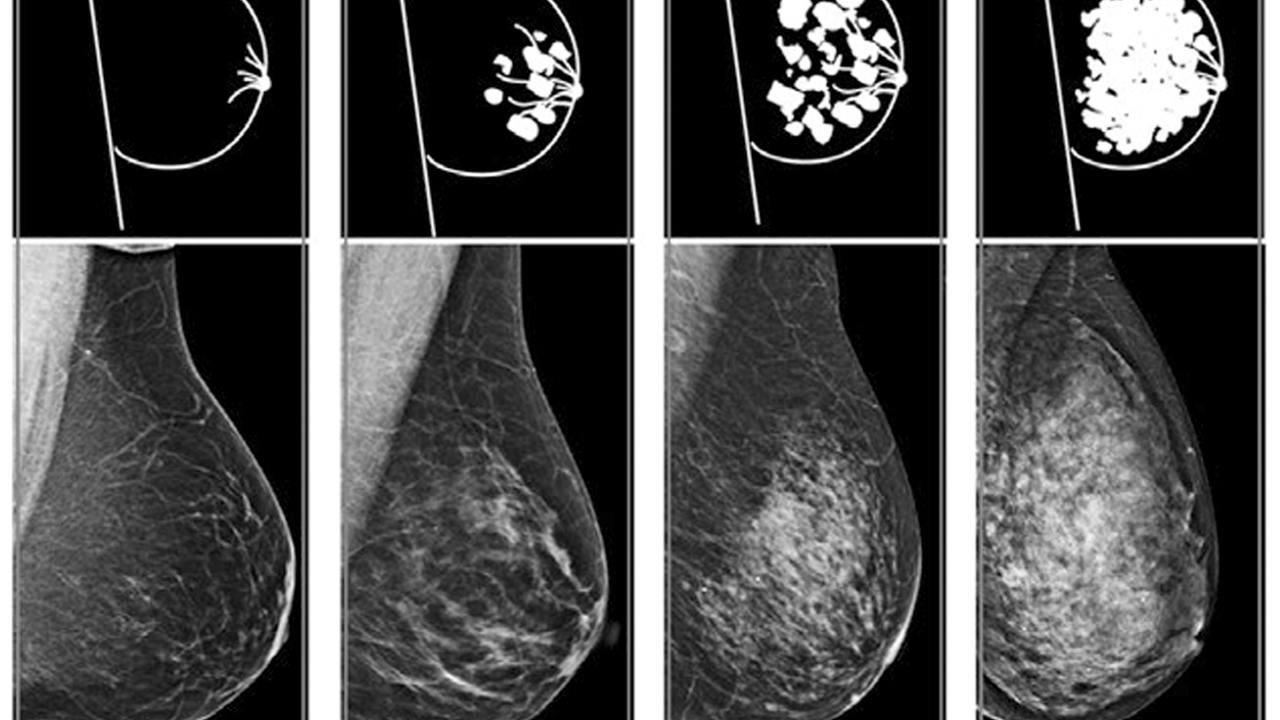

BI-RADS 1 kategorisi, meme görüntüleme sonuçlarında herhangi bir patolojik bulguya rastlanmadığı anlamına gelir. Bu, memede kitle, kist, şüpheli mikrokalsifikasyon (küçük kireçlenmeler) veya başka bir anormallik bulunmadığını gösterir. Radyolog, meme dokusunun tamamen normal olduğunu ve herhangi bir ek incelemeye gerek olmadığını belirtir.

BI-RADS 2 kategorisi, memede saptanan bulguların kesinlikle iyi huylu (benign) olduğunu ifade eder. Bu kategorideki bulgular genellikle fibroadenom (iyi huylu meme tümörü), basit kist (içi sıvı dolu kesecik), lipom (yağ bezesi) veya bilinen cerrahi skarlar gibi kanserle ilişkisi olmayan lezyonlardır. Radyolog, bu bulguların tehlikeli olmadığını ve ek bir inceleme gerektirmediğini belirtir.